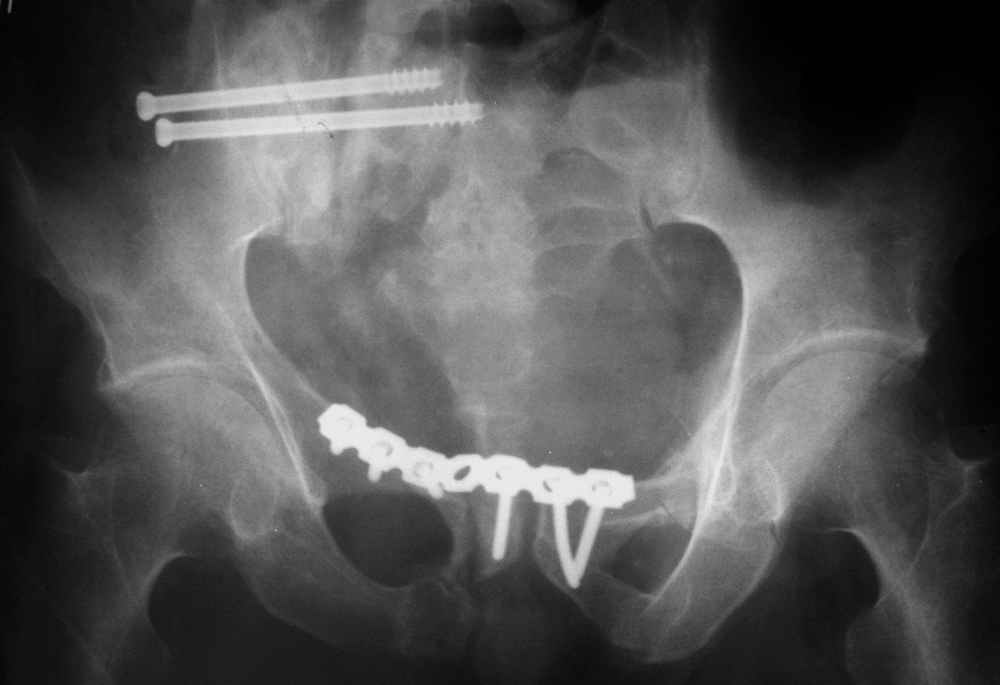

Пример лечения стабильной деформации с вертикальным смещением половины таза.

окончательная фиксация